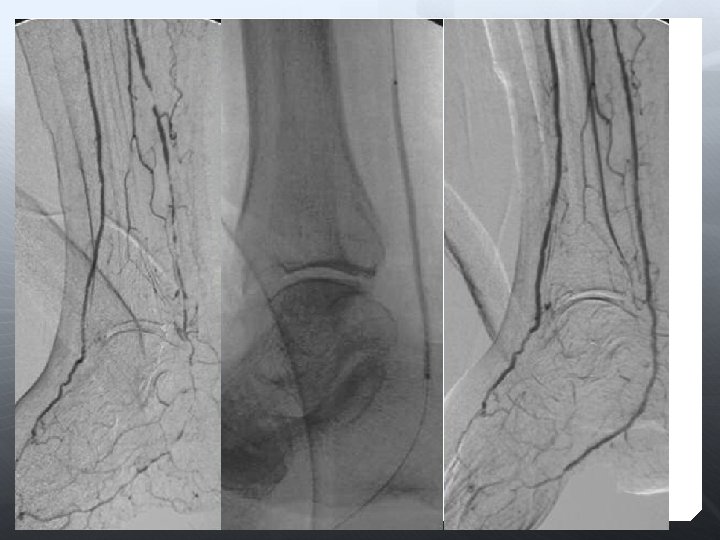

DİZALTI

Amaç uzun dönem açıklık değil, akımı restore etmek Olabildiğince çok damar restrore edilmeli Total ayak perfüzyonu iyileştirilir 3 damar run-off ile daha iyi SFA açıklığı sağlanır Oklüzyona karşı daha dirençli

Anjioplasti Subintimal anjioplasti Cutting-balon DEB Stent (BES, SES) DES Aterektomi Excimer laser